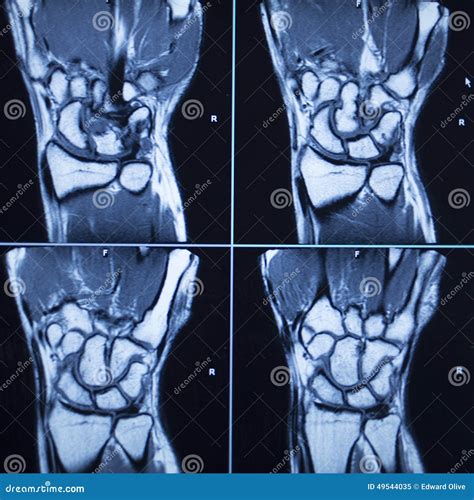

Understanding the intricacies of an MRI of hand can provide valuable insights into various hand conditions and injuries. Magnetic Resonance Imaging (MRI) is a powerful diagnostic tool that uses magnetic fields and radio waves to produce detailed images of the body's internal structures. When it comes to the hand, MRI scans offer a non-invasive way to visualize bones, muscles, tendons, ligaments, and other soft tissues with exceptional clarity.

An MRI of hand is a specialized imaging technique that focuses on the structures within the hand. This procedure is particularly useful for diagnosing conditions that affect the bones, joints, and soft tissues of the hand. Unlike X-rays, which primarily show bone structures, an MRI provides a comprehensive view of both hard and soft tissues, making it an invaluable tool for orthopedic and rheumatologic evaluations.

The MRI Procedure

The MRI procedure for the hand is typically performed in an outpatient setting and takes about 30 to 60 minutes. Here is what you can expect during the procedure:

• Positioning: You will be asked to lie on a table that slides into the MRI machine. Your hand will be positioned comfortably within a coil that helps capture the images.

• Imaging: The MRI machine will produce loud knocking or tapping noises as it captures images. You will be given earplugs or headphones to reduce the noise.

• Staying Still: It is crucial to remain still during the procedure to ensure clear and accurate images. Any movement can blur the images and require a repeat scan.

• Communication: You will be able to communicate with the technician through an intercom system if you need to stop the procedure for any reason.